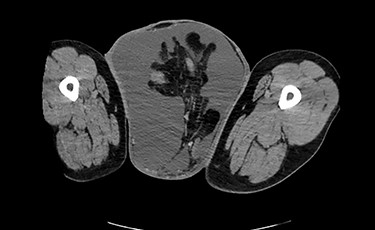

Testicular ultrasound revealed a large left inguinal hernia with a fluid-filled hernia sac surrounding one or more segments of the intestine within the scrotum, measuring >15 cm. The left testis could not be identified. The right testis appeared normal on imaging but was displaced superiorly and medially by the large left scrotal hernia sac. The right testis demonstrated color Doppler signals and arterial Doppler waveform. Computed tomography (CT) revealed a large left inguinal hernia sac with bowel, fluid and Left ureter within it associated with left-sided hydronephrosis and severe cortical thickening. Figures 2 and 3 demonstrate pertinent CT images.

CT (axial view) demonstrating large left inguinal hernia sac containing bowel, fluid and left ureter.